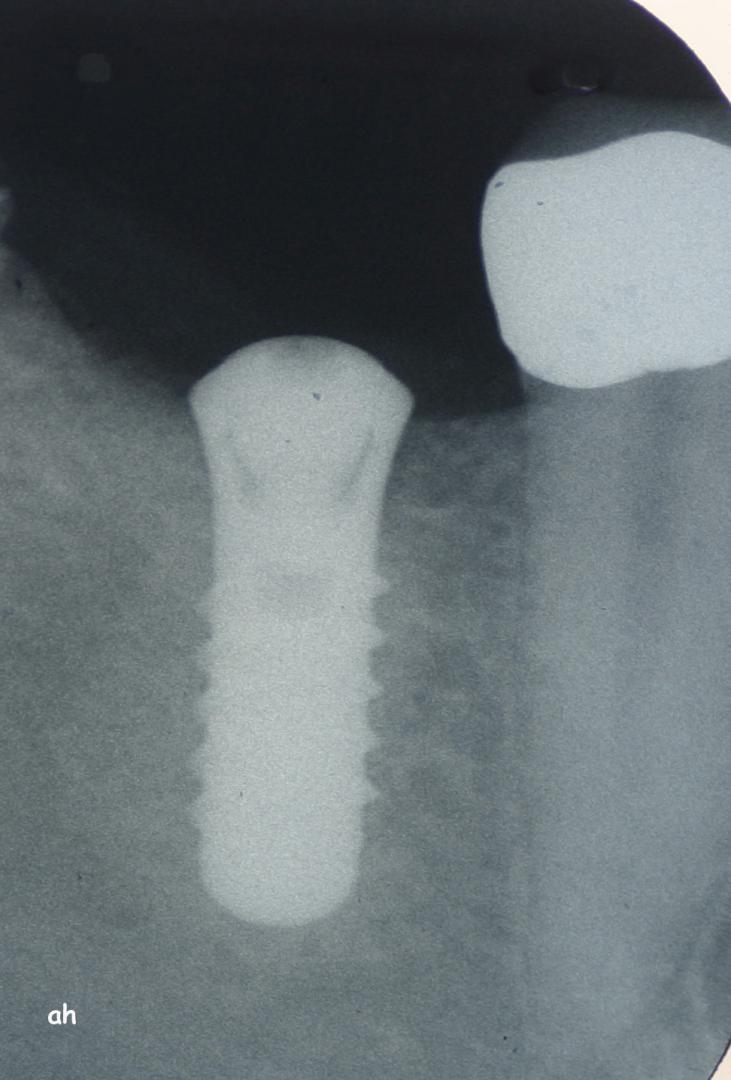

Exemple 14: Il est prévu de mettre un implant entre la molaire et prémolaire, mais le sinus se trouve à moins de 4 mm de la surface. Il faut donc relever le sinus avec une greffe d'os

Exemple 14: Un petit puits d'accès est créé afin d'atteindre le sinus, notez la membrane sinusienne.